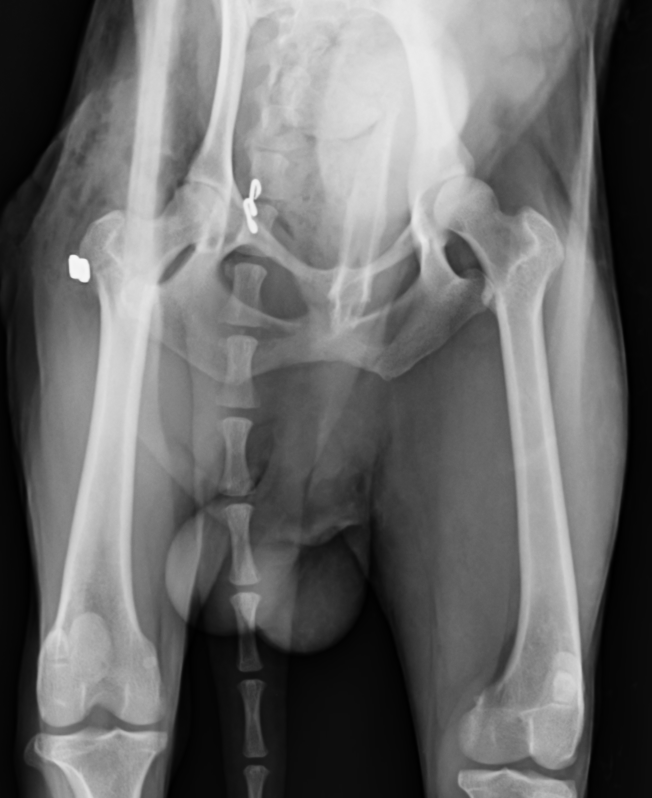

股関節が脱臼すると強い疼痛を引き起こし、足を地面に着けることができなくなり挙上してしまいます。股関節脱臼は脱臼する向きによって大きく2つに分けられます。90%が頭背側脱臼というもので、前方かつ、上方に脱臼してしまうタイプです。残りの10%が尾腹側脱臼というもので後方かつ、下方に脱臼してしまうタイプです。治療には用手による整復と、手術による治療がありますが、用手による整復の成功率は非常に低いとされており、基本的に手術によって整復します。頭背側脱臼ではワッシャーによる固定またはトグルピン法、骨頭切除などの術式が選択できます。症例によって治療法を選択しますが、可能であれば骨頭を切除せずに戻すのが理想と言えます。骨頭を切除すると術後の機能回復に時間がかかるのと、機能が元のの70〜80%にとどまると言われているからです。

尾腹側脱臼では上記のワッシャーの方法は使用できず、トグルピン法か創外固定法、大腿骨頭切除の方法を用います。トグルピン方は、骨盤臼に穴を開け、そこにトグルピンと呼ばれる特殊な形のピンを挿入し、そこに引っ掛けた人工靭帯を、大腿骨に貫通させた穴に通して固定する方法です。この方法も2週間ほど維持できれば安定化していきます。